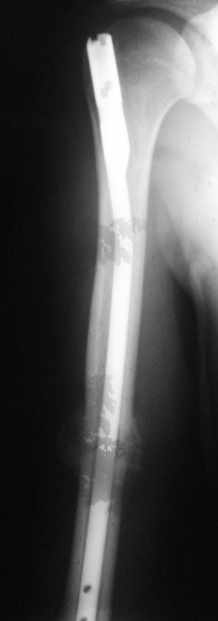

однозначно не блокировать и не убирать - есть прекрасная мозоль и все отлично срастается. Мне плохо видно - выступает ли гвоздь проксимально ( кажется, нет, гвоздь строго в уровень с костью)?

Если гвоздь хоть чуть-чуть выступает - убрать гвоздь как можно скорее (месяца через 3 после травмы), если не выступает - оставить все как есть

Большая мозоль - здоровый организм УСПЕШНО компенсирует недостатки фиксации.

Раз есть боль в области плеча - скорее всего, таки травмируется ротаторная манжета плеча гвоздем - либо подождать еще месяцок и гвоздь убрать, пока он больному не разорвал манжету "в клочья", либо (в идеале, если есть желание, операционное время, инструмент того же производителя, которым пользовались в Склифе, понимание со стороны больного и т.д) - забить гвоздь на полсантиметра глубже и заблокировать одним проксимальным шурупом, чтоб предотвратить его миграцию в канале

Само же состояние перелома мне не внушает никаких сомнений или опасений

Гвоздь для плеча - дело не очень хорошее, и, честно говоря, на этих снимках показаний к такому методу лечения я никаких не вижу. Больше процент несращений, часто (до 20-30 процентов) встречаются осложнения со стороны плечевого сустава... Однако, это уже выходит за пределы обсуждаемой темы

Обычное дело, пусть разрабатывает давно, лучше с методистом. Тут по снимкам проблем не видно. Винты вводить необязательно - если хирург знает, что делает. Например, если получился хороший press-fit из-за несоответствия формы гвоздя и канала.